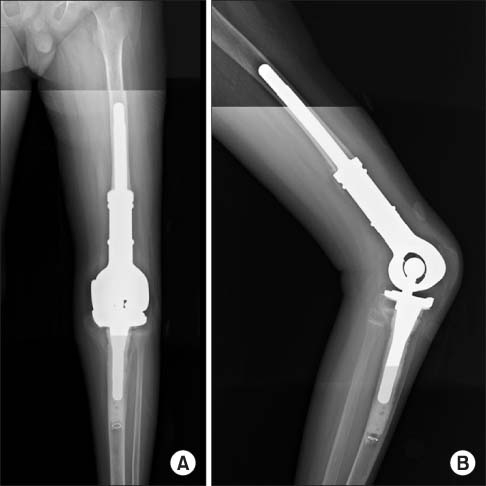

- Bone graft or prosthesis implant when necessary.